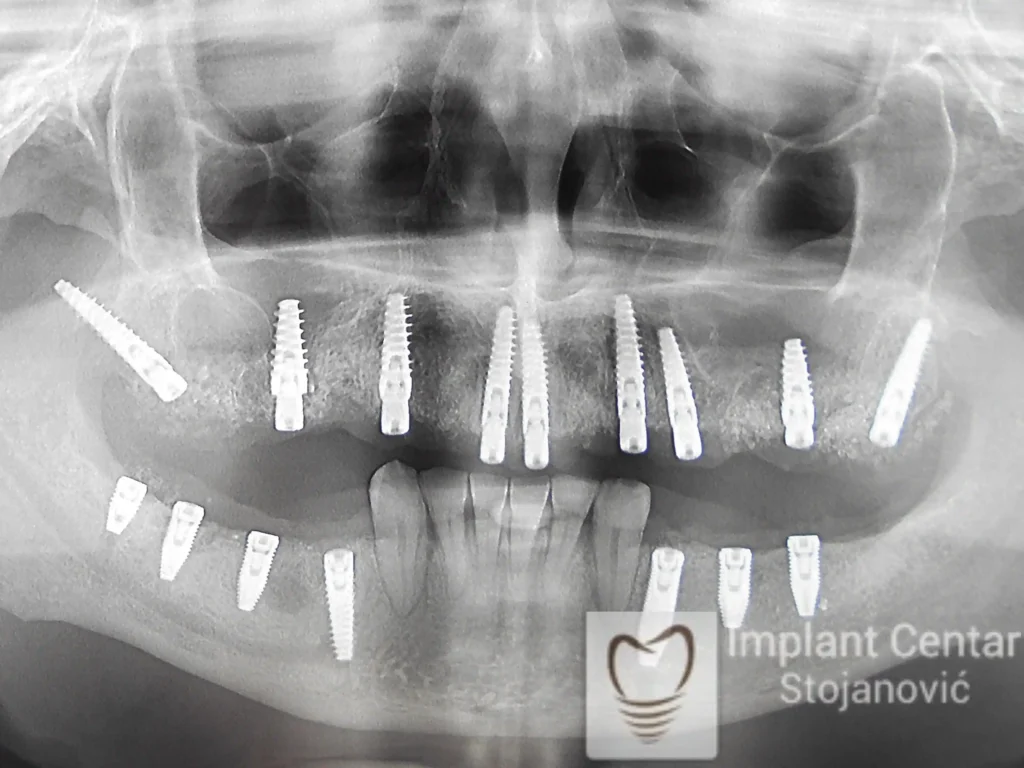

Ugrađeno je deset implantata u gornjoj vilici, u raspoloživu kost uz dodavanje veštačke kosti, od čega su dva tuberopterigoidna implantata. Ovim pristupom izbegnuta je potreba za sinus liftom, a postignuta maksimalna stabilnost.

Veći broj implantata omogućio je ravnomeran prenos žvačnih sila i izuzetnu stabilnost budućeg fiksnog rada.

U donjoj vilici su istovremeno izvađeni svi preostali zubi i ugrađeno je osam implantata.

• Ukupno je u gornjoj vilici ugrađeno 10 implantata kako bi se obezbedilo ravnomerno opterećenje pri žvakanju, a u donjoj vilici 8 implantata, što je omogućilo optimalnu stabilnost.